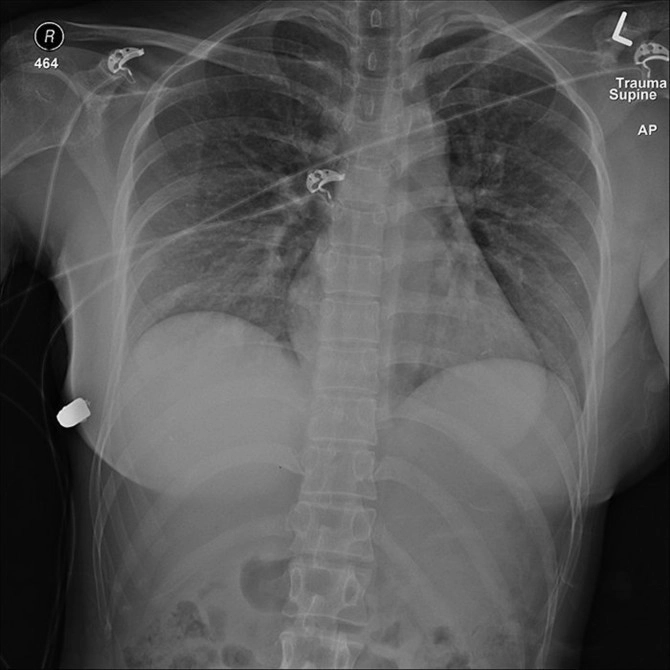

30-летней жительнице Онтарио удалось избежать смерти также благодаря силиконовой груди. Женщина возвращалась домой поздно вечером, когда вдруг почувствовала жар и боль в левой части грудины, затем она увидела кровь. Оказалось, что в нее выстрелил неизвестный человек. Оба импланта пришлось удалить, девушка отделалась лишь сломанным ребром. Мотивы и личность стрелявшего не были установлены.